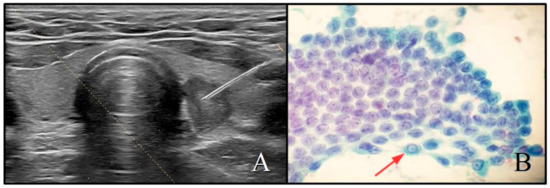

2.2. Ultrasound Evaluation

2.3. Cytopathology and Histopathology